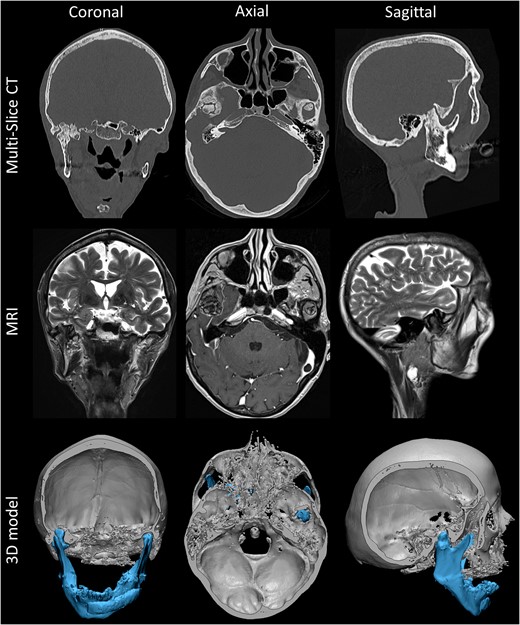

Clinical examination confirmed limitation of mandibular mobility with 16 mm interincisive mouth opening, 2 mm right-sided laterotrusion and inability for left-sided laterotrusion or protrusion. An Angle class II.1 malocclusion was present. The lower dental midline had undergone a right-sided shift, an occlusal cant was present as well as a right-sided crossbite. Extra-oral examination revealed facial asymmetry with skewing of the menton towards the right side and a short posterior facial height. A panoramic radiograph illustrated extensive dysplasia of the right condyle–fossa complex (Fig. 1). Additional CT and MR imaging was performed. These confirmed upward condylar displacement of 11.5 mm into the middle cranial fossa on the right with extensive osseous remodeling and upward relocation of the right inferior temporal gyrus. Three-dimensional rendering using Mimics® medical image processing software and CT–MR image coregistration based on mutual information [2] were performed to add visual information regarding to the severity of the trauma (Fig. 2).

CT and MR skull imaging, using axial gadolinium enhanced T1-weighted and coronal and sagittal T2-weighted MR images, and related 3D model with mandibular segmentation and digital removal of the calvarium. Note the extent of remodeling and asymmetrical development throughout the subsequent years with even upward relocation of the right inferior temporal gyrus.